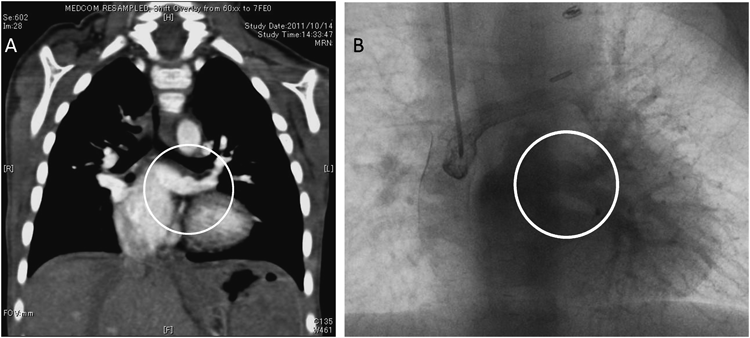

MDCT(multi-detector raw CT,multi-detector CT)検査(Fig. 1

Pediatric Cardiology and Cardiac Surgery 32(3): 215-220 (2016)

Fig. 1 Preoperative three-dimensional computed tomography shows the vertical vein (white arrow) connected to the hepatic vein

PDA, patent ductus arteriosus; HV, hepatic vein.

生後4日のMDCTでは,共通肺静脈は垂直静脈を経由して,肝静脈へ還流しており,この接続部位で軽度の狭窄を認めた.共通肺静脈径は7 mmで,左右肺静脈径は4 mmで左右差はなかった.また,右上気管気管支が観察された.脾臓は認めなかった.